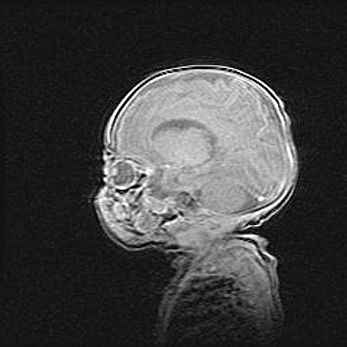

Церебральная ишемия II.

Возраст: 5 дней

Вес: 3400 г

Пол: женский

Окружность головы: 35 см

Срок гестации: 39 недель

Церебральная ишемия – это заболевание, характеризующееся недостаточностью (гипоксией) либо полным прекращением (аноксией) снабжения мозга кислородом по причине закупорки одного или нескольких сосудов. Это приводит к  что метаболическим расстройствам различной степени тяжести в тканях головного мозга, развитию коагуляционных некрозов и гибели нейронов.